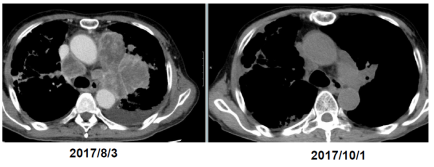

東京大学医学部附属病院において進行再発非小細胞肺癌15例に対してゾレドロン酸誘導 γδ T細胞を用いた免疫細胞治療を施行した(UMIN試験ID:C000000336)。6回投与終了4週間後の時点で6症例が病勢の安定(stable disease, SD)、6症例が病勢進行(progressive disease, PD)、判定不能3例であり、病勢コントロール率は40.0%であった。中央生存期間は589日であり、中央無増悪生存期間は126日であった。そこで、非小細胞肺癌に対するγδT細胞治療の無増悪生存期間を評価・検討することを目的に第II相試験として先進医療を開始した。慶應義塾大学病院を加え2施設でγδT細胞治療を提供した。

本試験は、標準治療抵抗性の肺がん患者に対するγδ T細胞治療の評価を目的に、肺がんに対するサードラインの治療として試験をデザインした。しかしながら、分子標的薬及び免疫チェックポイント阻害剤の登場で肺がんに対する標準治療が大きく変化し、多岐にわたる新規治療薬が承認されるたびに、本治療へのエントリーが後ろに回り、ラストラインの治療としてほぼベストサポーティブケアになった患者を対象患者とせざるを得なかった。すでに複数の肺がん治療を受け、病勢が進行して非常に厳しい状態で本試験への候補として紹介される事例では、PSの低下が著しくエントリーには不適格と判断された。特に平成27年12月に、「切除不能な進行・再発の非小細胞肺癌」に対して、抗PD-1抗体(ニボルマブ)が承認されて以降、多くの肺がん患者がニボルマブ治療の効果を期待して、γδ T細胞治療への参加前にニボルマブ治療が組み込まれて新規症例の試験への組み込みが遅延した。本試験はニボルマブ併用治療ではないが、体内に残存するニボルマブがγδ T細胞に及ぼす影響が明らかになっていなかっため、血清ニボルマブ消失半減期(13±7日)を用いてニボルマブ投与歴のある患者は、ニボルマブ最終投与日から3ヶ月間のwash-out期間をあけてγδT細胞治療を開始し、試験治療開始後も注意深く経過観察を行うこととした。進行肺がん患者にとって、3ヶ月は非常に厳しく、この間に病勢の進行やPSの低下でエントリーが困難になった。また、先行治療の影響で半数以上の症例では培養困難に陥り、エントリー症例数が限定されてしまった。予定症例85例に対して25例の実施にとどまってしまったが、ニボルマブに続いてペンブロリズマブ、アテゾリズマブ等の免疫疫チェックポイント阻害剤が承認され、肺がんの標準治療が大きく変化したため、対象患者の再設定を含めた試験デザインの再考が必要と考え、本試験を終了した。

従来の治療法に抵抗性を有する非小細胞肺がんに対して、ゾレドロン酸を用いて患者自己末梢血単核細胞から誘導したγδT細胞を用いた免疫療法は、目標症例数未達で終了となり、有効性を示すことはできなかったが、安全に実施することが可能であった。強い免疫反応とともに腫瘍縮小を認めた症例を経験し、本治療法のPOCが再確認できた点は非常に有意義であった。

γδT細胞治療は、単剤治療としては、セカンドラインで肺がん治療に用いられる化学療法剤や分子標的薬と同程度の効果を認めた。免疫チェックポイント阻害剤(ICI)と異なる作用機序を持つ本治療は、今後ICIとの併用治療あるいは、ICI無効例・抵抗例を対象として治療法として、試験デザインを再考し評価したい。